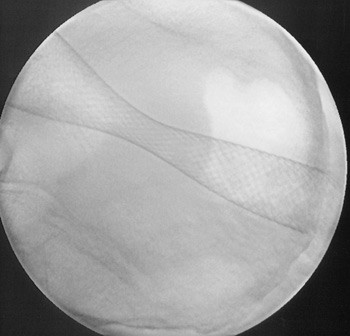

Figur 1  b) Kontrollbilde ved hjelp av gjennomlysning etter utfolding av stent. Foto Stavanger universitetssjukehus